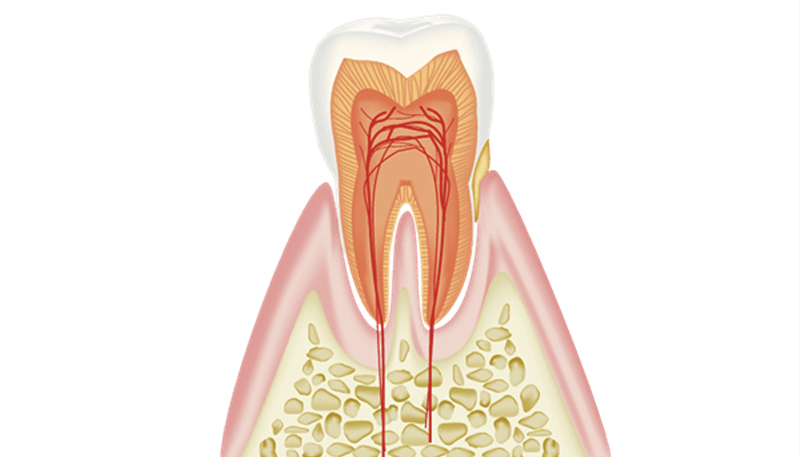

- 歯周病とは

歯と歯茎の境目に汚れが溜まる事で歯茎が腫れている状態を言います。

歯肉炎ではまだ骨は溶けていません。

歯ブラシなどで歯茎から血がでやすいのが特徴です。

歯肉炎・歯周病になる原因

全ての人は健康な歯茎からスタートします。 健康な歯茎に細菌性のプラーク(汚れ)が溜まると歯肉炎になります。 歯肉炎はプラークが溜まれば全ての人がなります。 ところが歯肉炎の状態からさらにプラークが溜まっても、歯周病になる人とならない人がいます。 これには宿主反応(個人の免疫力)が大きく関係しています。 汚れがいっぱいついていても歯周病にならない人もいれば、汚れが少量しかついていないのに歯周病が進行してしまう人がいるのはこのためです。 歯肉炎=プラークですが、歯周病=プラーク+宿主反応です。 タバコ、糖尿病、生活習慣病などが歯周病を悪化させる修飾因子となります。